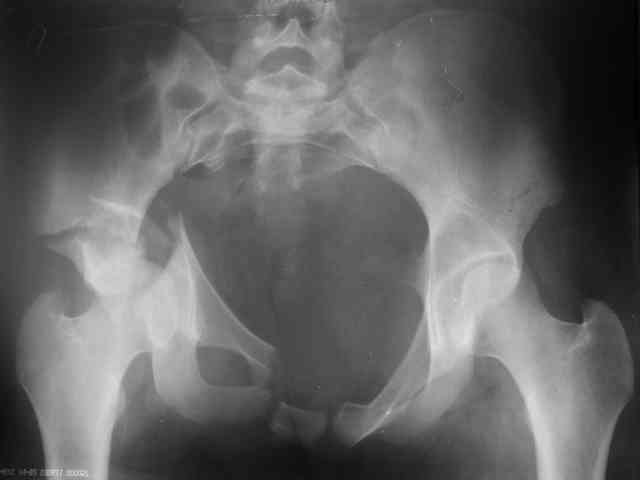

P.S. в приложении R пациентки с похожей проблемой доступа.. за исключением того, что перелом

двухколонный. Вертлугу лечили Y доступом.